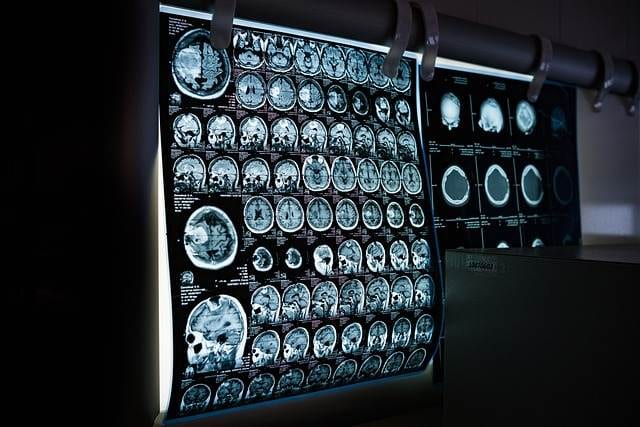

Facharzt für Neurologie (Nervenheilkunde). Er behandelt körperliche Störungen des Nervensystems. Dieses benötigen wir zum Beispiel zur Informationsübertragung im Körper („Befehle“ an Muskulatur, Rückmeldungen von Sinnesorganen wie zum Beispiel dem Ohr). Hier finden wir fließende Übergänge zum medizinischen Fachgebiet der Psychiatrie. Typische Erkrankungen zur Behandlung beim Neurologen wären z.B. Epilepsie, Multiple Sklerose, Parkinson, Alzheimer-Demenz und andere.